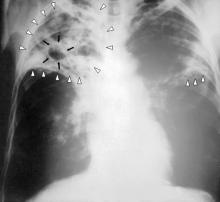

Obesità

Le terapie possono essere integrate con dieta e attività fisica, ma non bastano da sole. Il documento sottolinea l’importanza di equità nell’accesso, prevenzione e cure personalizzate, avvertendo sui rischi di farmaci falsificati